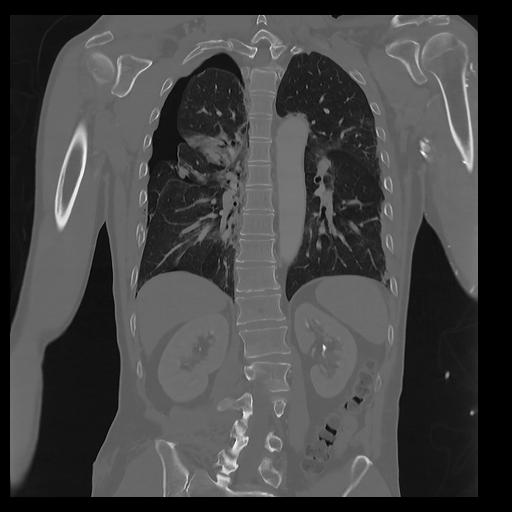

32 PULMON,CE,Coronal,3.000,PULMON,Coronal,